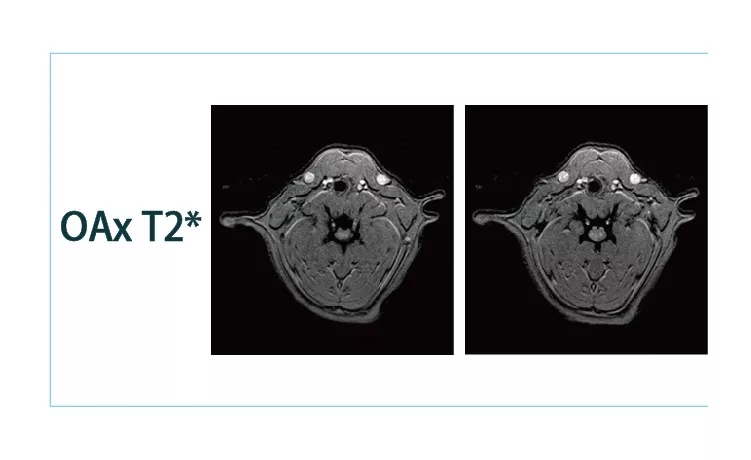

【朗润影像档案】20181221磁共振影像病例结果讨论